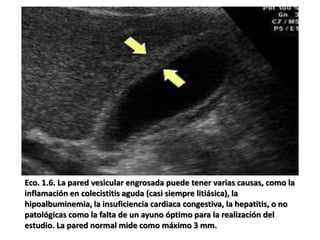

Eco. 1.6. La pared vesicular engrosada puede tener varias causas, como la

inflamación en colecistitis aguda (casi siempre litiásica), la

hipoalbuminemia, la insuficiencia cardiaca congestiva, la hepatitis, o no

patológicas como la falta de un ayuno óptimo para la realización del

estudio. La pared normal mide como máximo 3 mm.